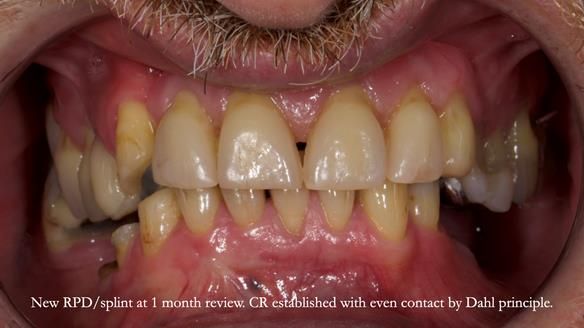

Keith’s case was one of the most challenging and rewarding cases I’ve treated this year. This 64 year old man presented with ill-fitting acrylic partial dentures that lacked stability, retention, and aesthetics. They constantly broke. He had lost the upper front teeth in a road traffic accident in his early 20s. The unopposed teeth had erupted, taking up space. After careful planning, we made a durable, metal-based upper partial denture/splint to address his dental concerns. He loved the outcome.

I also used the Dahl concept to re-establish the occlusion upon fitting the RPD, which helped to intrude the lower left canine without needing to grind it too much.